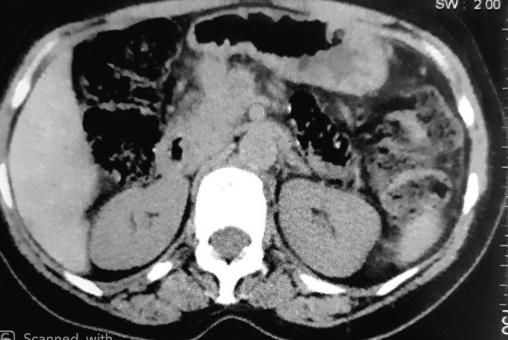

Cette femme de 54 ans consultait pour un nodule ombilical associé à des douleurs de l’hypochondre gauche, et une anorexie depuis 4 mois. À l’examen, cette tuméfaction ombilicale était douloureuse et ferme (fig. 1 ). La tomodensitométrie thoraco-abdomino-pelvienne (fig. 2 et 3 ) montrait un processus tumoral du corps du pancréas avec infiltration de la graisse périlésionnelle, métastases hépatiques et carcinose péritonéale. L’imagerie par résonance magnétique notait un processus tumoral nécrotique du corps du pancréas avec métastases hépatiques et nodules péritonéaux carcinomateux. La biopsie cutanée du nodule montrait une lymphangite carcinomateuse dermique avec des cellules tumorales carcinomateuses en petits amas dans les lymphatiques et un foyer d’infiltration épidermique pagétoïde, concluant à une lymphangite carcinomateuse dermique. Ce nodule dit de Sœur Marie-Josèphe révélait un adénocarcinome pancréatique. La patiente décédait 3 mois plus tard.